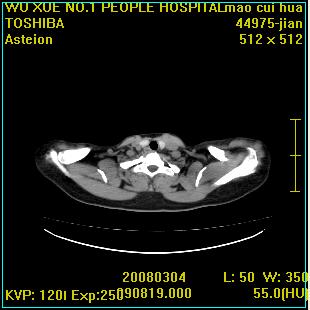

标题: CT12025:男,50岁,左肩活动受限半年。

肩关节骨质破坏呈小囊状,其周软组织轻度肿胀,余未见异常。

考虑:肩袖损伤。建议mri。

左侧肱骨头密度不均匀,高低混杂,周围软组织略肿胀,考虑结核性病变。

左侧肱骨头密度不均匀,高低混杂,髓腔密度稍高,周围软组织略肿胀,肌间隙模糊,考虑慢性骨髓炎可能。密切结合临床!

肩关节周围软组织轻度肿胀,肌间隙模糊,余未见异常。

考虑:肩周炎。